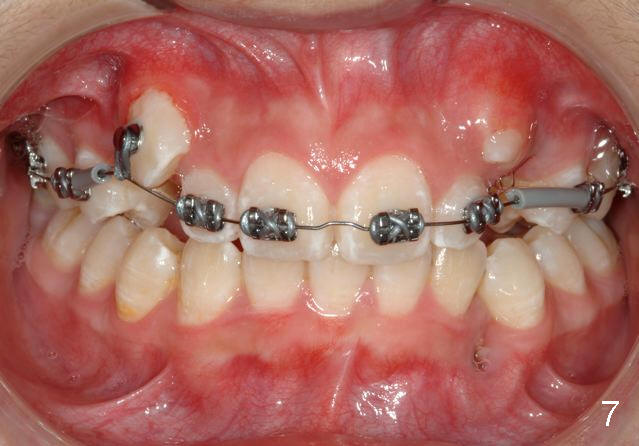

Great job removing the teeth, especially #22.  I placed the braces on the upper teeth on Tuesday.  Toby had a terrible cough (poor guy) and it was quite challenging as a result.  Just imagine seeking that perfect bracket placement in between coughs!!!  So, we will place the lowers another day and permit more healing of the #22 site.  I hope you guys had a nice Thanksgiving.  Have a great weekend.  Tim

P.S. I do not take the first small gauge NiTi AW back to the 7s at appointment #1, to A) make sure of a good 7 bond (as they are most difficult to isolate), B) to prevent a wire poke if a 7 should come off, and C) minimize the chance of a very flexible AW pulling out of the 7.  If the 7s are still bonded at appointment #2, I trust I have a good bond and then include the 7 with every subsequent AW change.  I thought I would share that little tip with you:-)

We are teasing tooth #6 down initially with a light elastic force. This will minimize any reciprocal forces on the anterior teeth. I do not want to intrude the incisors while extruding 6. That would potentially open the bite.